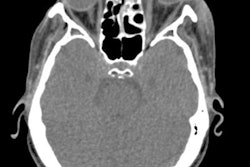

Calcium hydroxide was injected beyond the girl's tooth apex during a root canal, leading the patient to experience severe pain and a change in skin color on her cheek near her molar. The patient also experienced swelling, bruising, and paralysis.